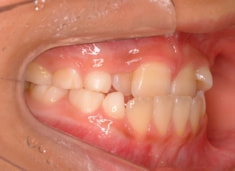

小児期ケース:反対咬合+上顎両側3番埋伏歯

(受け口+3番目の永久歯が左右両方とも埋まってしまい、はえてこない)

治療法:上顎急速拡大装置+クリアスナップ+フェイスマスク+上顎3番は開窓牽引CT写真にて位置確認

治療前

治療開始時